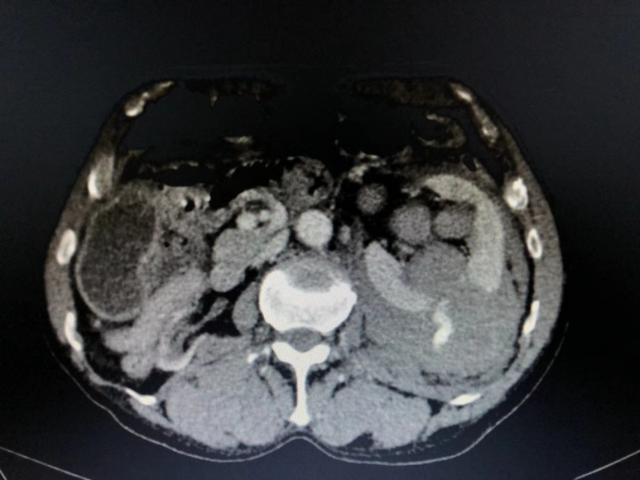

(术前CT示右肾慢性严重萎缩,左肾挫裂血肿、腹膜后血肿,多发肋骨骨折等)

患者左肾破裂大出血并休克,必须马上止血或者做左肾切除术,以保全患者生命。但对于此位年轻患者而言,右肾从CT上来看已经萎缩功能丧失,左肾作为唯一的好肾,肯定不能切除。因此,尽量保存左肾组织功能尤显重要。目前病人处于濒危状态,外科手术创伤大且手术风险及预后效果不确切。对于该患者治疗方案的选择非常棘手。